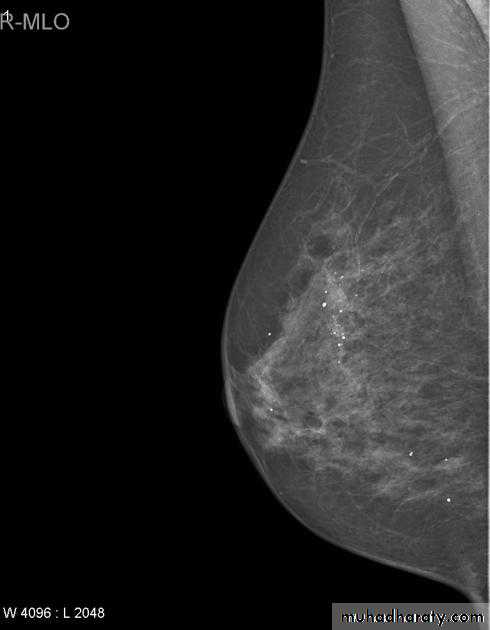

Micro calcifications

Micro calcifications are tiny specks of calcium in the breast. Micro calcifications seen on a mammogram are of more concern than macrocalcifications, but they do not always mean that cancer is present. The shape and layout of microcalcifications help the radiologist judge how likely it is that cancer is present.

In most cases, the presence of microcalcifications does not mean a biopsy is needed. But if the microcalcifications have a suspicious look and pattern, a biopsy will be recommended. (During a biopsy, the doctor removes a small piece of the suspicious area to be looked at under a microscope. A biopsy is the only way to tell if cancer is really present.)